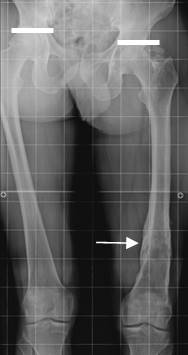

Fig 131. Acortamiento.

Rx telemétrica en AP. Fractura consolidada sobre el fémur izquierdo, que ocasiona acortamiento de la extremidad.